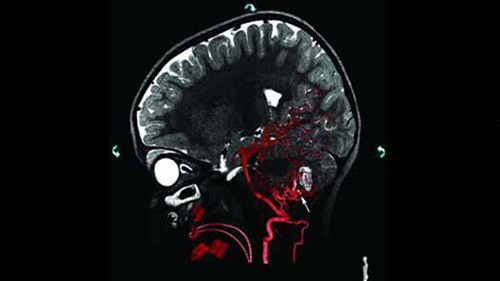

Live 3D MR/CT Roadmap fuses live 2D fluoroscopy on a pre-acquired MR or CT image, which may reveal hidden anomalies and enable real-time motion compensated navigation to support interventional procedures. Live 3D MR/CT Roadmap provides full 3D view for guidance of guidewires, catheters and coils through complex vessel and anatomical structures.

Live 3D Roadmap allows you to follow the advancement of guidewires, catheters and coils in real-time. It automatically adapts in real-time to changes in C-arm angulation and rotation, table movement, field of view and source-image distance.